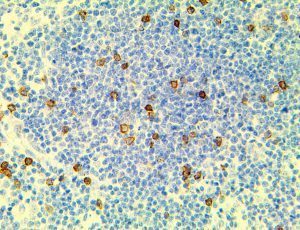

It is the ICU physician who is most likely to witness one of the deadliest manifestations of the abnormal immunological response, the cytokine storm syndrome (CSS). This response is also referred to by some as the cytokine release syndrome (CRS). CSS is characterized by continuous activation and expansion of macrophage and lymphocyte populations, which secrete large amounts of cytokines, causing the cytokine storm. This massive cytokine release is akin to hemophagocytic lymphohistiocytosis (HLH) disease, a syndrome characterized by initial unchecked and persistent activation of cytotoxic T lymphocytes and NK cells.

Clinical and laboratory manifestations of HLH include fever, enlarged liver and/or spleen, neurologic dysfunction, coagulopathy, liver dysfunction, cytopenias (i.e., low levels of erythrocytes, leukocytes, and/or platelets), hypertriglyceridemia, hyperferritinemia, hemophagocytosis, and eventually diminished NK cell activity as the immune system becomes progressively paralyzed. HLH can be familial (primary HLH) or secondary to another disease process (sHLH), such as rheumatic disease, in which it is referred to as macrophage activation syndrome (MAS, characterized by elevated ferritin).